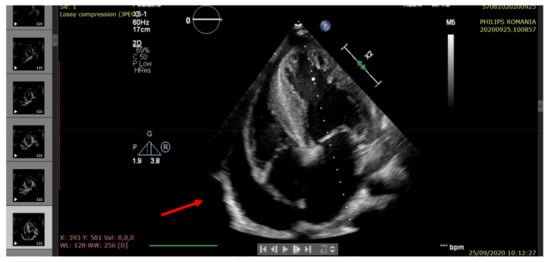

| Right ventricular ejection fraction RV EF (%) | >60 | 55 | 50 | 55 | 45 |

| Left ventricular ejection fraction LV EF (%) | >60 | 60 | 35 | 45 | 25 |

| Pericardial fluid (edge) | <5 mm | Small (6 mm) | Raised (20 mm) | Moderate (14 mm) | Large (22 mm) |

| Pulmonary hypertension (echocardiographic criteria) | Normal | Mild | Moderate | Mild | Moderate/severe |